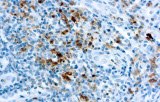

- Linfoma di Hodgkin classico: le cellule tumorali sono tipicamente CD30+ e spesso CD15+, con PAX5 debole e CD20 negativo nelle grandi cellule tumorali.